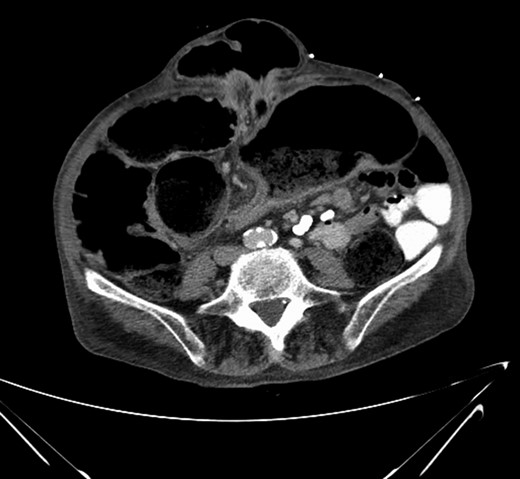

Mr. X had a plain film abdominal x-ray taken in ED which displayed dilated loops of bowel, Fig. 2. CT abdomen and pelvis was performed which showed an abrupt transition point in the sigmoid colon and a twisting of the sigmoid colon consistent with a volvulus, Fig. 3.

CT abdomen/pelvis. Note large umbilical hernia with loops of bowel within. Note abrupt transition point at centre of Image.